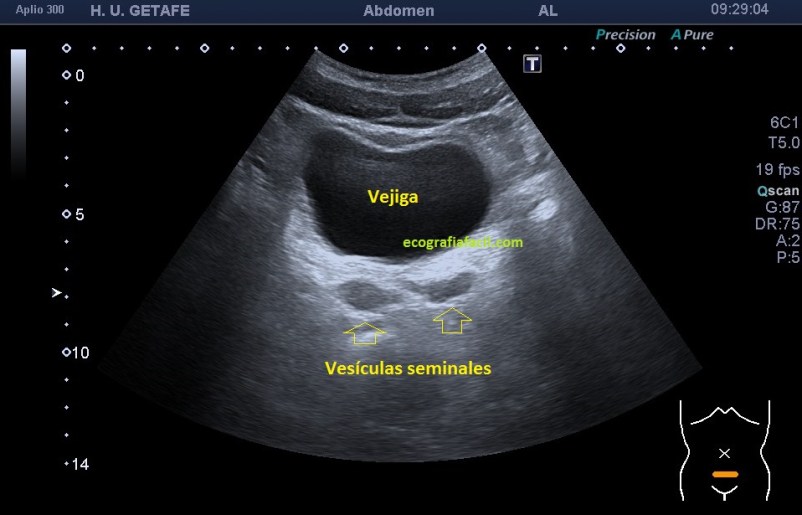

La ecoarquitectura no es visible en todos los estudios, de modo habitual, lo normal es que no se vean. Pero en ocasiones y por motivos fisiológicos evidentes, éstas se objetivan perfectamente como dos ecoestructuras más o menos ovaladas a ambos lados de la parte posterior de la vejiga. En función de su repleción estas vesículas se verán más o menos, repito, cuando se vean.

Es importante que conozcas la normalidad, para eso te muestro la imagen 1, para que te sirva como referencia. No es una imagen de una calidad extraordinaria, solo la hice para mostrar que la ecoestructura era visible y que era rigurosamente normal.